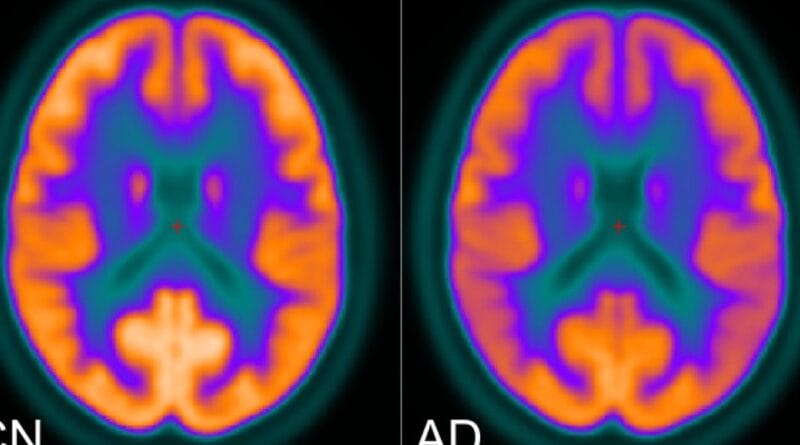

Otro de los docentes que está investigando en inteligencia artificial aplicada a la salud es Gonzalo Uribarri, del KTH Royal Institute of Technology en Estocolmo, Suecia, que lo hace en colaboración con especialistas del Hospital Universitario Karolinska, uno de los más grandes de Europa. Específicamente, están usando estas tecnologías para tratar de desarrollar un sistema que permita acelerar el diagnóstico de enfermedades neurodegenerativas, como el Parkinson y el Alzheimer. Para ello, exploran alternativas basadas en el análisis de señales cerebrales (electroencefalografía/EEG y magnetoencefalografía/MEG) y el seguimiento ocular (eye tracking), tecnologías que miden la actividad eléctrica cerebral y los movimientos del ojo.

“Estos datos, casi imperceptibles para el ojo humano, son procesados mediante algoritmos de machine learning para identificar patrones asociados a enfermedades”, afirma Uribarri y aclara que el trabajo de investigación incluye varias instancias: primero es necesario ordenar y “limpiar” los datos que reciben, que son tomados en un contexto clínico, y luego deben entrenar al algoritmo para que pueda detectar si los datos responden a una persona con alguna de esas enfermedades.